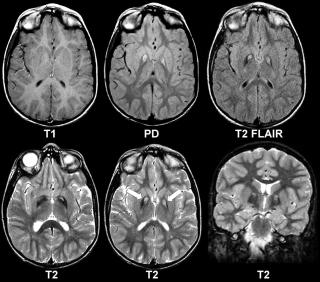

На МРТ Т1-зависимого типа и невриномы, и нейрофибромы изо- или слегка гипоинтенсивны по отношению к спинному мозгу. Однако, встречаются случаи и повышенного сигнала за счет сокращения Т1 мукополисахаридами, связанными с водой. Протонная плотность повышена, а на Т2-зависимых МРТ они чаще неоднородные, могут быть очень яркие участки, где имеется высокое содержание воды, и сравнительно низкого сигнала, особенно в центре. Обе опухоли хорошо контрастируются. По форме невриномы округлые, границы ровные, четкие. При МРТ видно, что нейрофибромы вытянуты вдоль корешка. Размеры могут быть самыми различными.